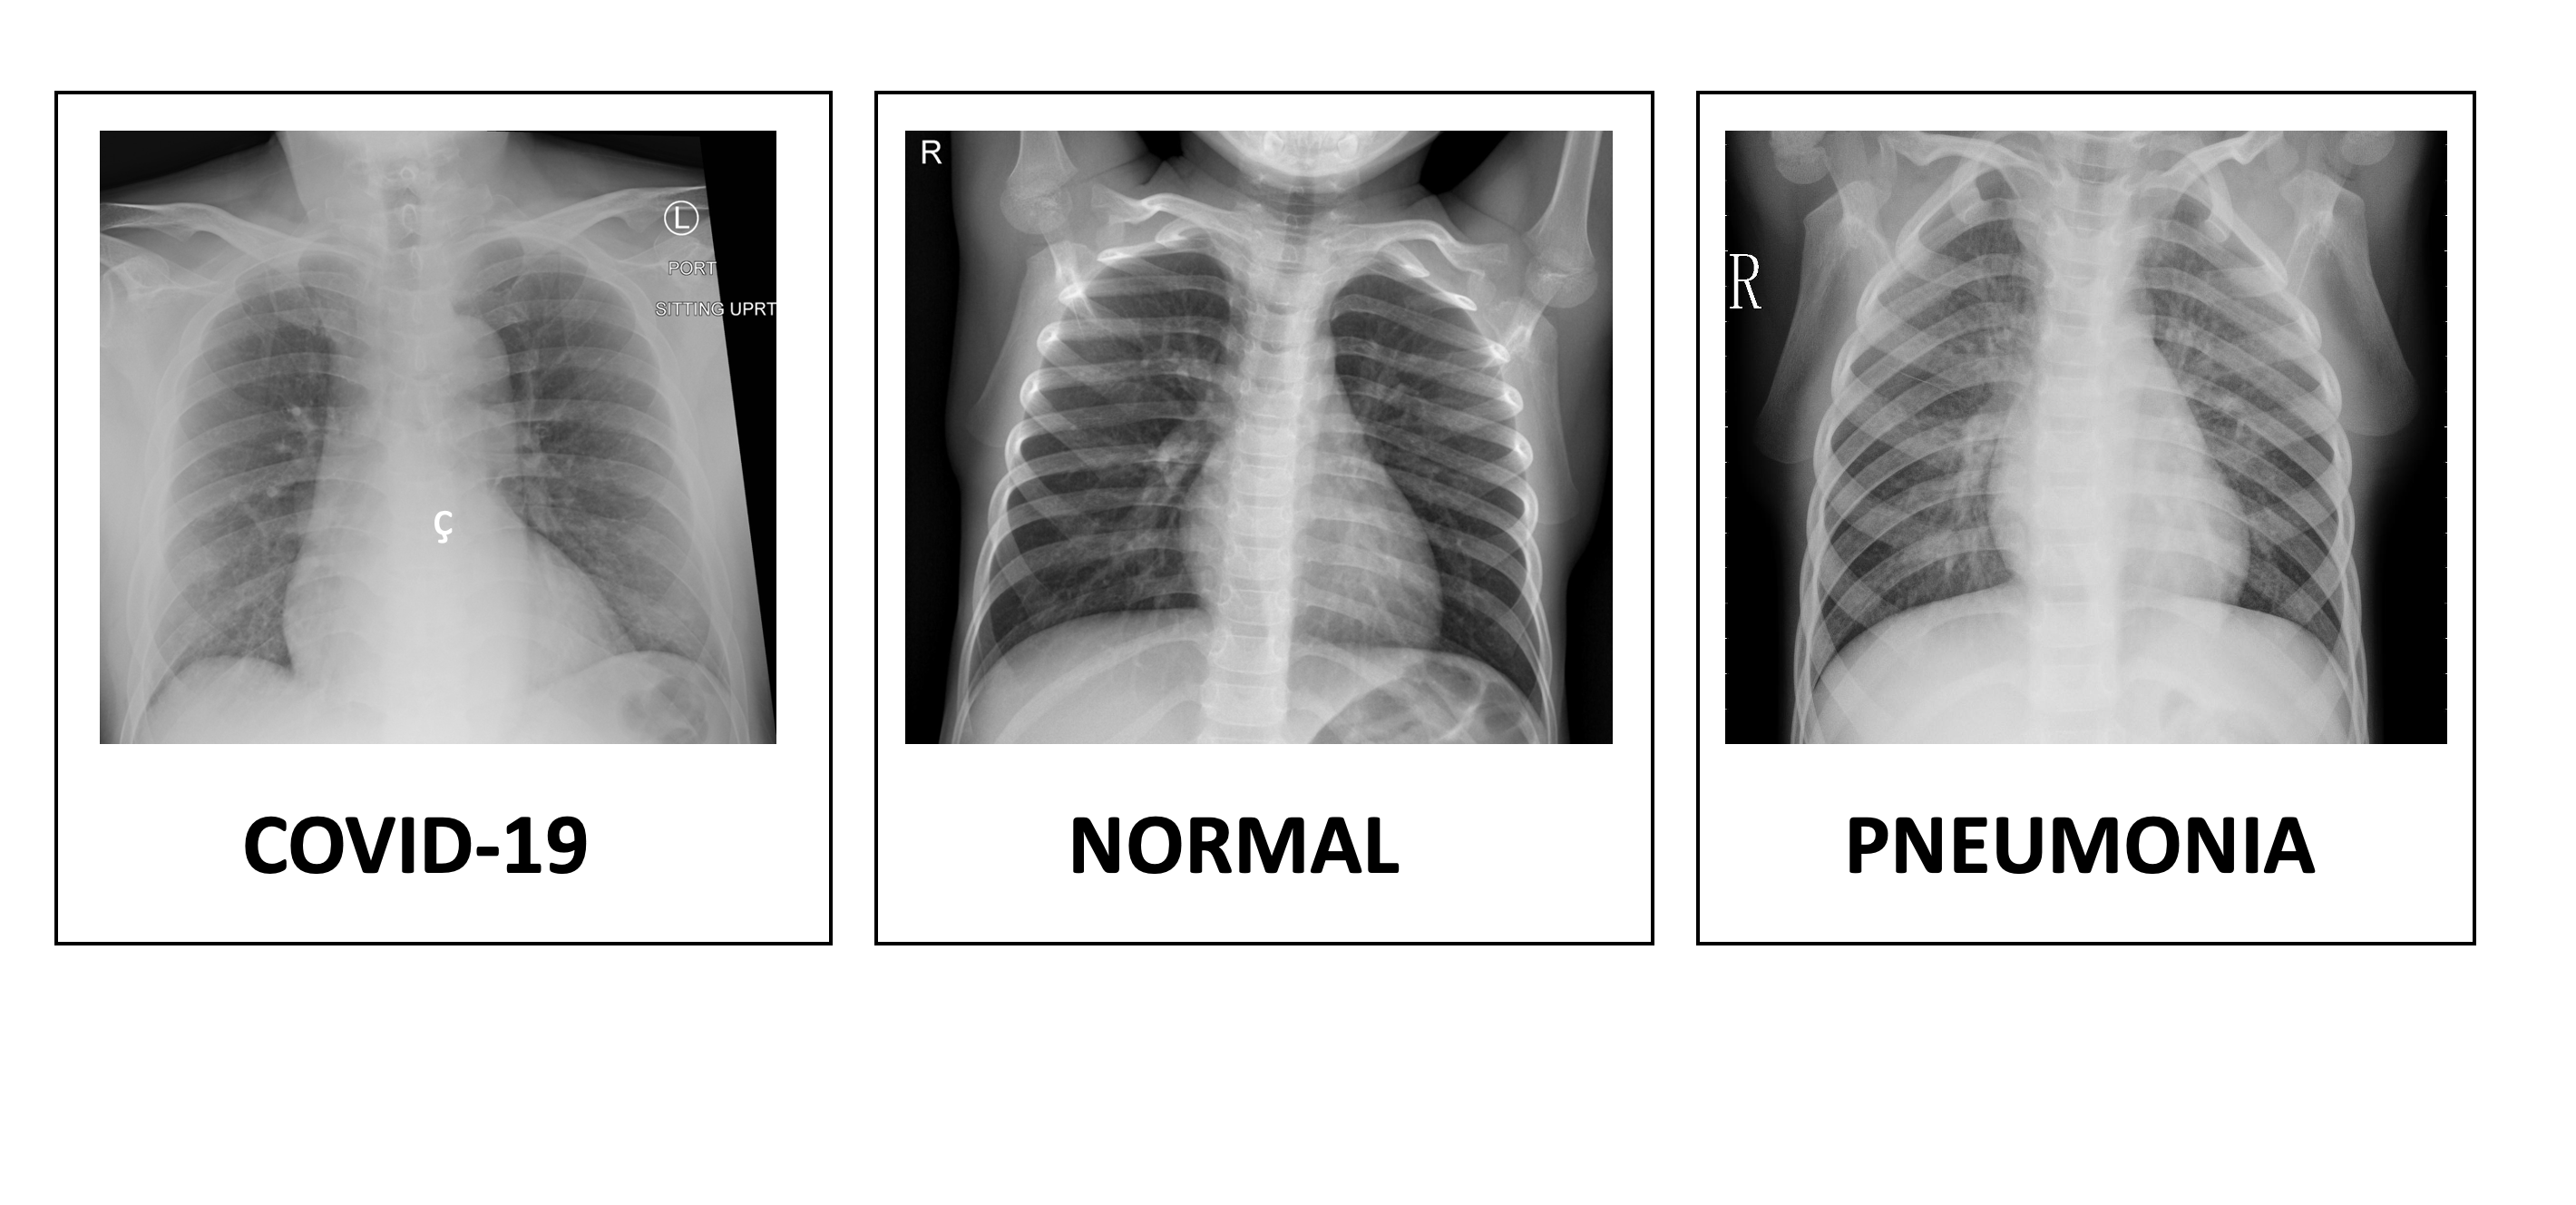

Un modelo de aprendizaje automático personalizado basado en Tensorflow con la ayuda de un radiólogo experto, que sería capaz de diferenciar entre Covid-19. Para este ejemplo, he entrenado este modelo con conjuntos de datos públicos de imágenes de Covid-19 disponibles en Kaggle y Google. Casi 442 imágenes de rayos X de Covid-19, 1263 imágenes de rayos X normales y 3295 imágenes de rayos X de neumonía.

Muy simple, vamos a construir un sistema de IA conversacional que acepte una imagen de rayos X y envíe esa imagen a un modelo de aprendizaje automático basado en Tensor Flow personalizado que analizará la imagen de rayos X y predecirá si es normal, neumonía o Covid-19. Y vamos a alojar este bot basado en SAP Conversational AI en WhatsApp, por lo que será muy fácil de usar porque casi todo el mundo usa WhatsApp.